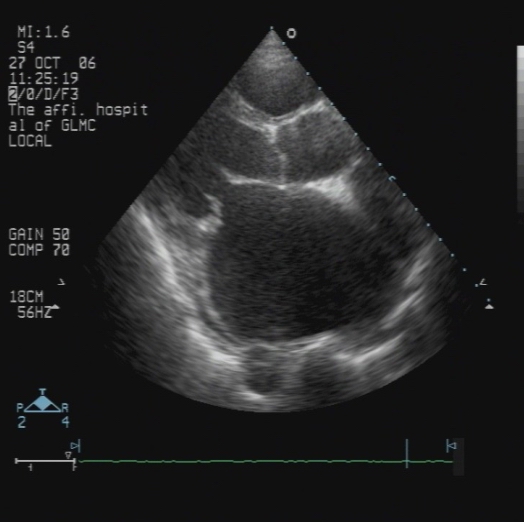

心脏彩超:

● RVOT:33mm,AOV:30mm,LAS:72mm,RAS:65mm,LAD:61mm,LVPWD:10mm,IVS:10mm,RVD:22mm,EF:0.67,FS:30%。全心增大,主动脉瓣反射增强,余瓣膜柔软不厚,闭合良好,室间隔与左室后壁不厚,呈逆向运动。房室间隔连续性完整。

提示:全心大